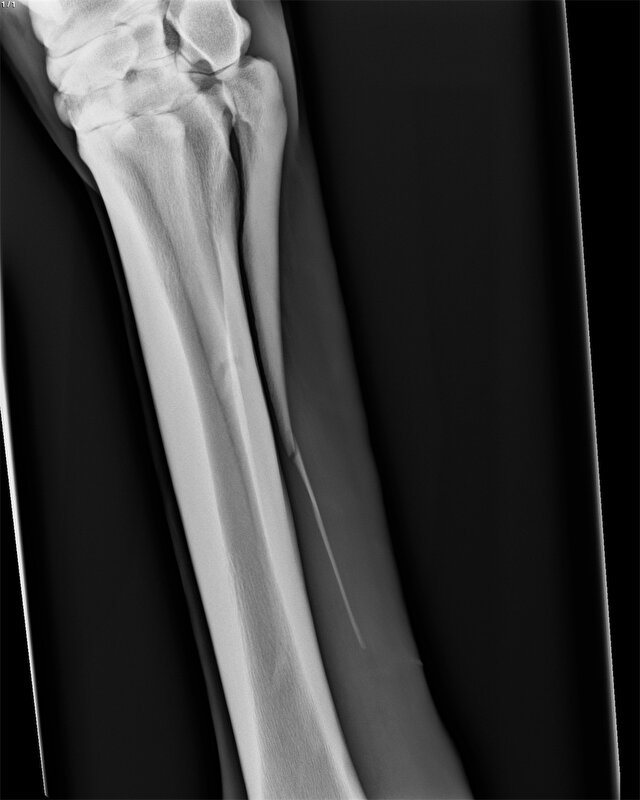

Icecrystal schreef:Mijn paard had precies dezelfde breuk als op jouw foto. Been bleef maar dik, verder niet kreupel.

Ik heb haar in Utrecht laten opereren voor rond de €1000,- . Een week boxrust en daarna de wei op. Na 2 weken wei was alles mooi slank en zijn we weer gaan opbouwen!

[ [url=m/uxbEy6.jpg]Afbeelding[/url] ]